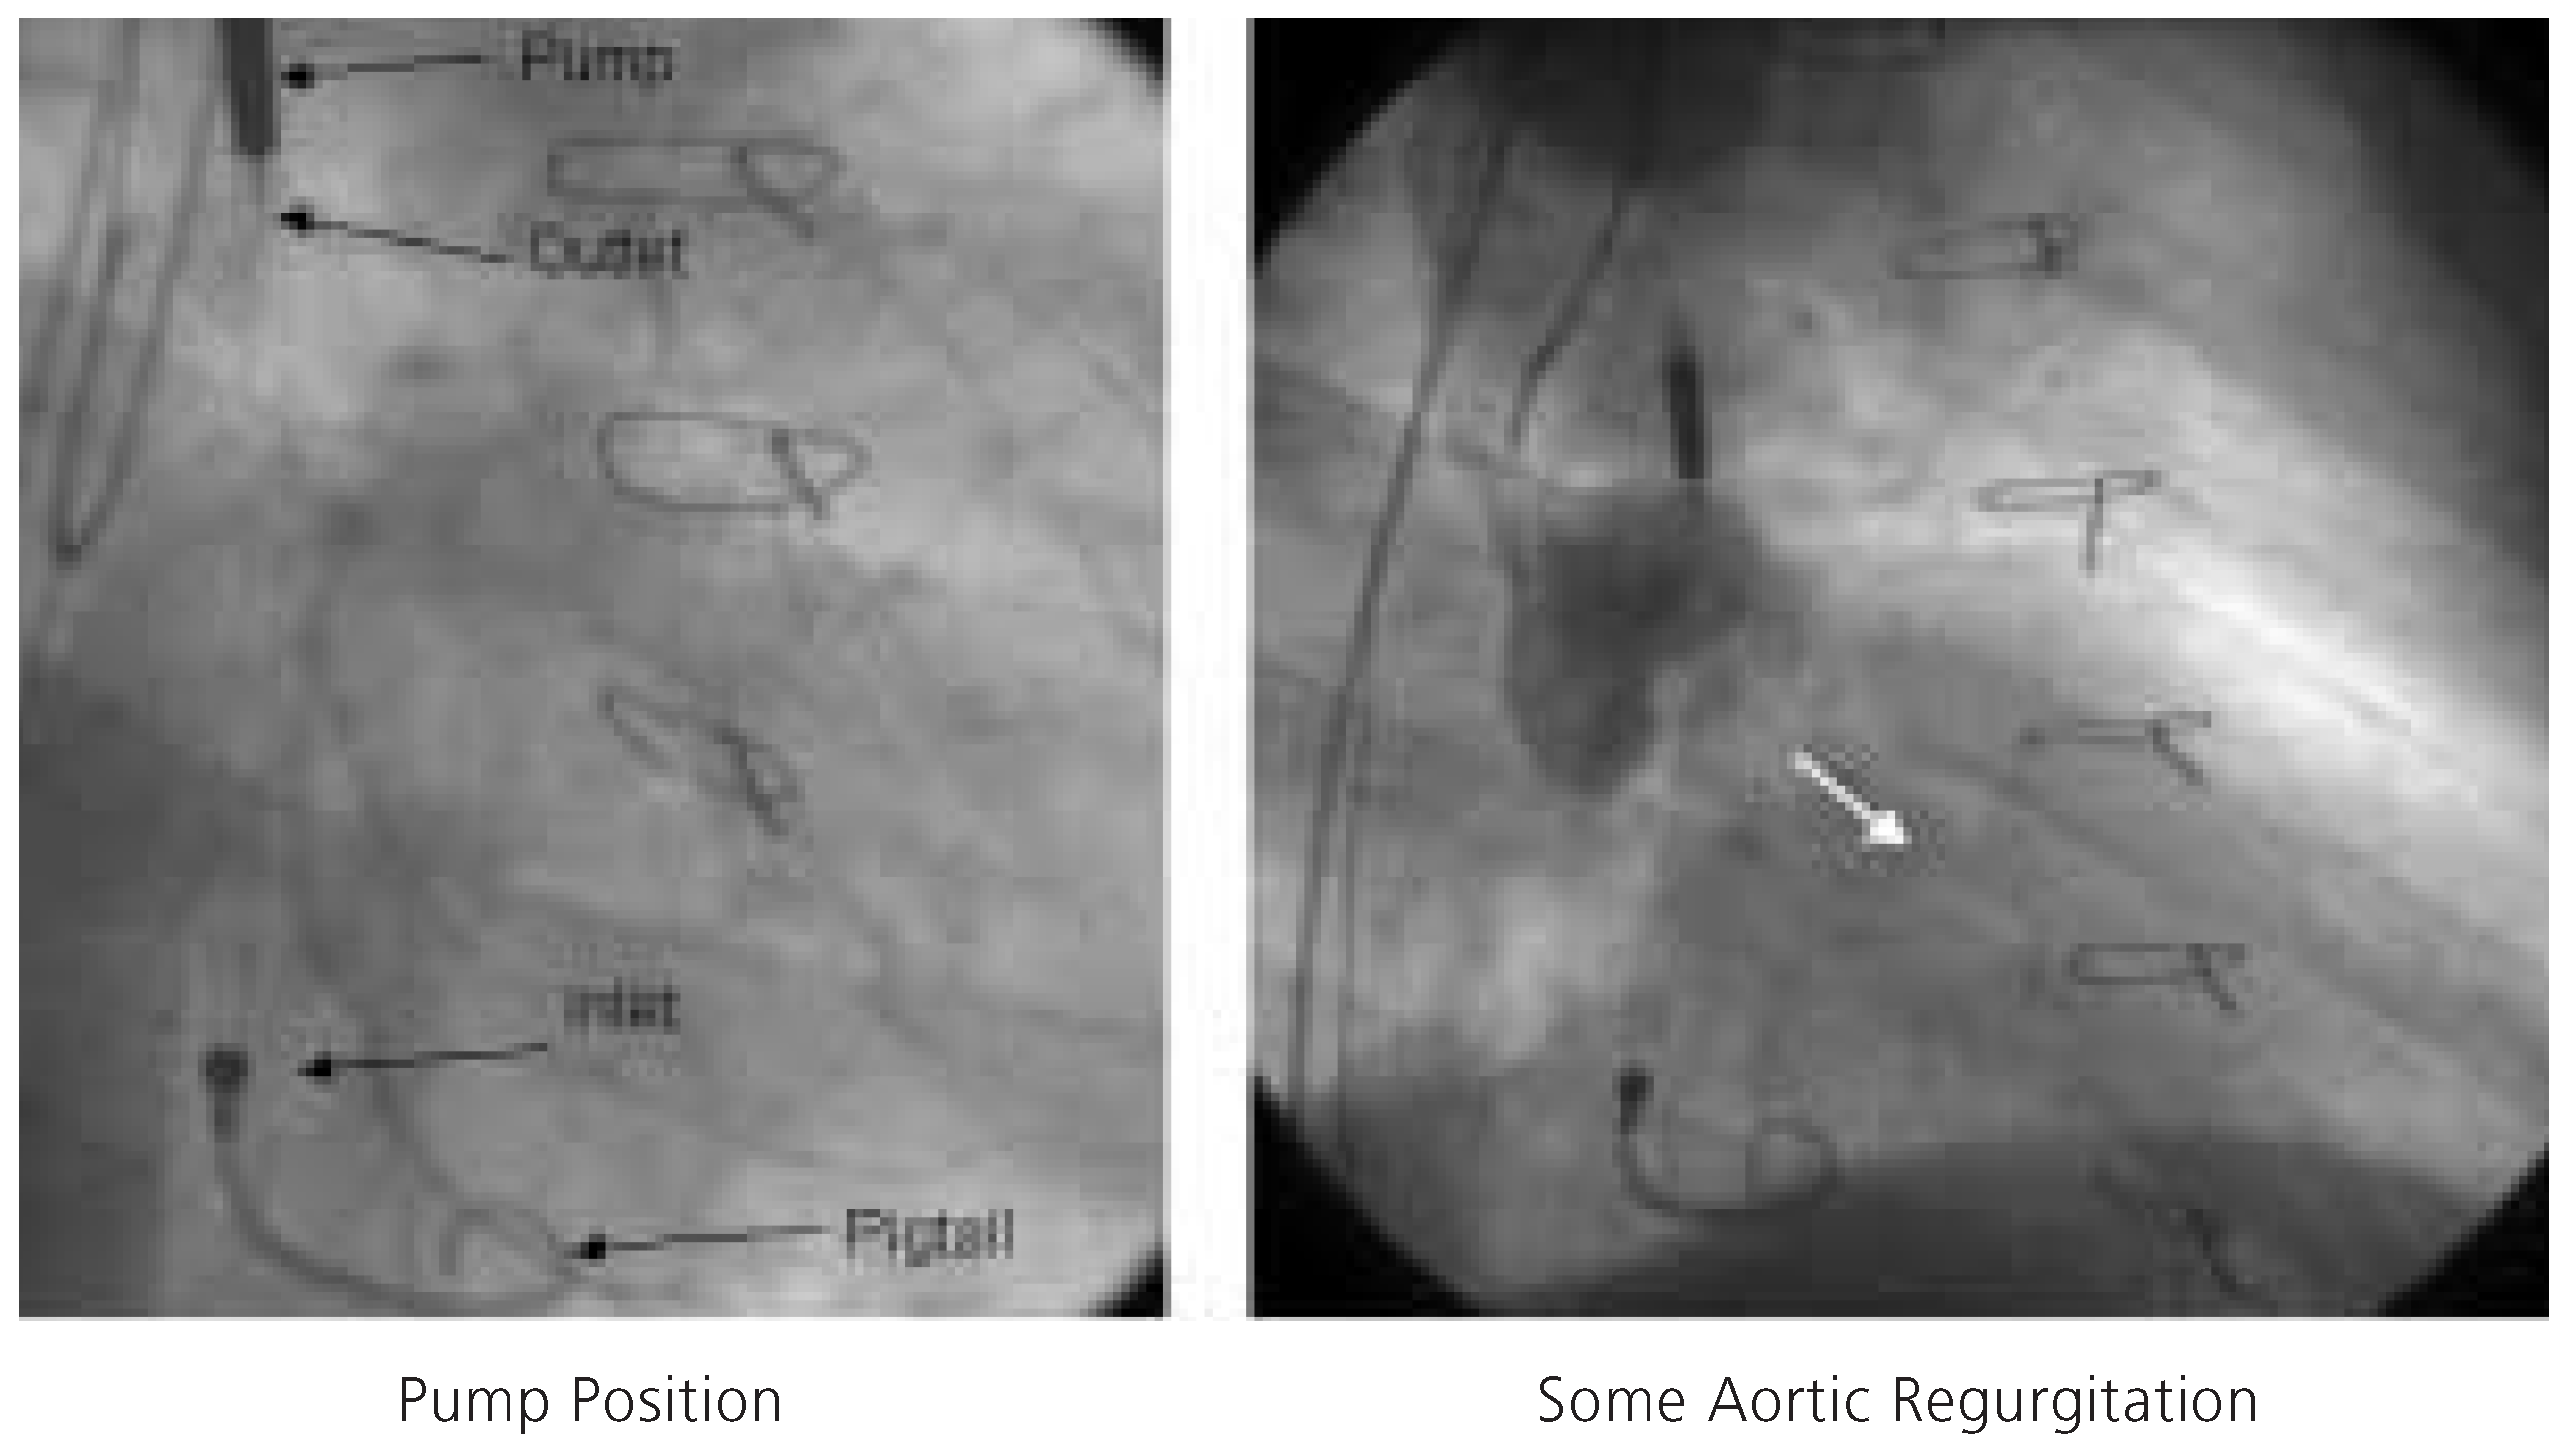

Figure 4.

Fluoroscopic appearance of the Impella Recover® LP 2.5 pump (left). Angiographic evidence of aortic regurgitation during aortography engendered by the 12F catheter traversing the aortic valve (right).

Since the patient refused cardiac transplantation and due to clinical evidence of ischaemia, percutaneous coronary intervention of the native left circumflex artery was planned. In light of the severely diminished LV function, the elevated filling pressure despite intensive heart failure and diuretic therapy, and documented viability in the area to be intervened, percutaneous coronary intervention was considered high risk. Following written informed consent, the decision to perform an Impella Recover® LP 2.5-assisted percutaneous coronary intervention was made on December 7th, 2004. Both groins were used for vascular access. Following local anesthesia, a 13F peel-away sheath was placed into the right femoral artery. Systemic anticoagulation was achieved with administration of unfractionated heparin (70 U/kg), and the patient was pretreated with acetylsalicylic acid 100 mg/d and clopidogrel 75 mg/d. First, a 5F pigtail catheter was positioned in the LV and then exchanged over a 0.014 inch guidewire for the 12F Impella Recover® LP 2.5 catheter. The correct position of the device was verified by cinefluoroscopy (fig. 4) and an electronic placement signal. Circulatory support was initiated at the highest pump speed (P9, approximately 2.5 l/min) and maintained throughout the intervention.

The initial case of a novel percutaneous LVAD proofed easy to implant and provided partial circulatory support during a high-risk percutaneous coronary intervention without complications. The principal advantage of the Impella Recover® LP 2.5 device over the TandemHeart™ (Cardiac Assist Inc, USA) [4] is its ease of implantation and the smaller catheter size (13F vs 17F). Moreover, there is no need for a transseptal puncture, and the retrograde insertion of the device over a guidewire through the aortic valve into the LV is familiar to all cardiologists. There is no extracorporeal blood and the central portion of the microaxial pump avoid the friction problem of the drive shaft of the Hemopump, the predecessor of the Impella device [5]. The motor of the Hemopump was outside the body and overheating of the device shaft had been one of its major drawbacks. The circulatory support provided by the Impella Recover® LP 2.5 is limited to 2.5 l/min, which does not suffice in patients without at least some LV function. The TandemHeart™ may deliver up to 3.5 l/min and completely replace LV function. Some aortic regurgitation is likely engendered by the 12F catheter traversing the aortic valve (fig. 4).